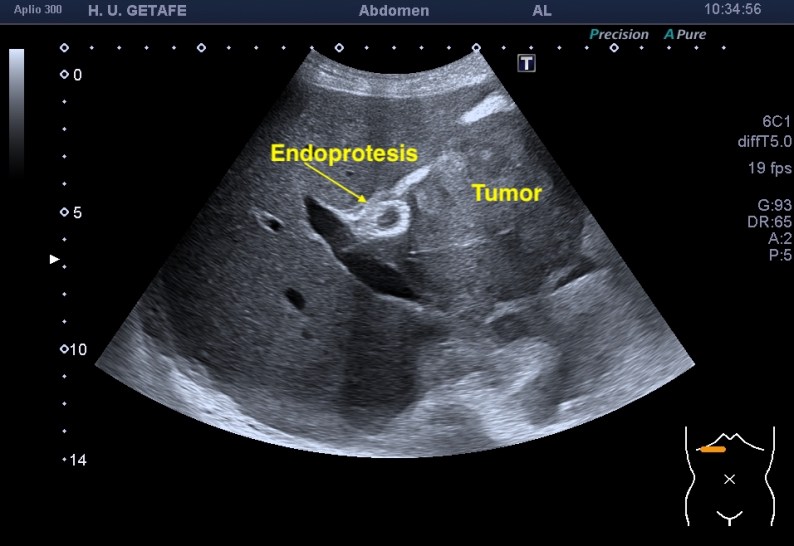

El estudio certificó que el Stent estaba bien posicionado y que el avance de la enfermedad mostraba una gran masa sólida hepática que sería la responsable de la nueva aparición de la ictericia.

Te enseño imágenes:

La endoprótesis se observa como una ecoarquitectura hiperecogénica con un entramado típico de los stents que se colocan en otras localizaciones cardiacas o aórticas. Se puede observa el aspecto rejilla típico, rodeado de una estructura hiperecogénica que es el cuerpo de la malla y que combate el aumento de la presión producida por el crecimiento de la masa tumoral.